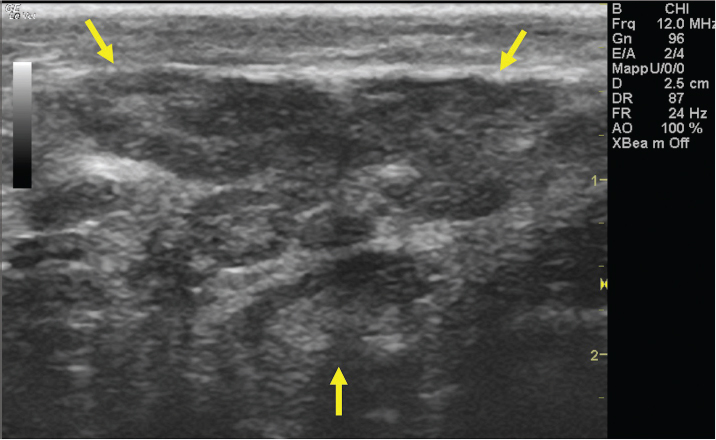

The left jugular vein appeared as an anechoic tubular structure which collapsed under the probe pressure, the color Doppler examination revealed normal blood flow within the vessel (Fig. 3). Bi-dimensional ultrasonography of the right jugular vein showed a heterogeneous, non-cavitating, hypoechoic structure occluding a narrowed right jugular vein for about 30 cm of length localized in the proximal and mid-portion of the neck compatible with a thrombus (Fig. 4). The color Doppler examination showed blood flow through the lateral portions of the thrombus in the cranial and mid-portions of the right jugular vein (Fig. 5). Cranially to the thrombus, a marked distension of the maxillary and linguofacial veins was evident, with a turbulent and echogenic flow; the latter was compatible with blood stasis near the thrombus (Fig. 6). Caudally to the thrombus, the right jugular vein presented reduced diameter, thickened walls, and normal blood flow (Fig. 7). The cranial part of the thrombus originated from a heterogeneous scare tissue, localized at the level of the right mandibular angle (Fig. 8). After injection of the first saline contrast bolus in a right facial vein, no microbubbles appeared in the right jugular vein, caudally to the thrombus, proving the presence of a complete right jugular vein occlusion. On the contrary, after injection of the second bolus, microbubbles were visualized in the left jugular vein as small, intense, echo signals within the vein lumen, demonstrating the presence of collateral circulation that drained the blood from the right facial veins to the left jugular vein (Fig. 9). Venography results confirmed the complete occlusion of the right jugular vein and the presence of submandibular venous collaterals that connected the right facial veins with the left jugular vein (Figs. 10 and 11). Based on the previous results, the diagnosis of JVT with complete occlusion of the vessel lumen was confirmed. The horse’s owner refused any proposed medical or surgical therapy.

Fig. 9. Bi-dimensional ultrasonographic image of the left jugular vein in longitudinal section (arrows). Microbubbles appeared as small, intense, echo signals that passed in the vein lumen following agitated saline injection.